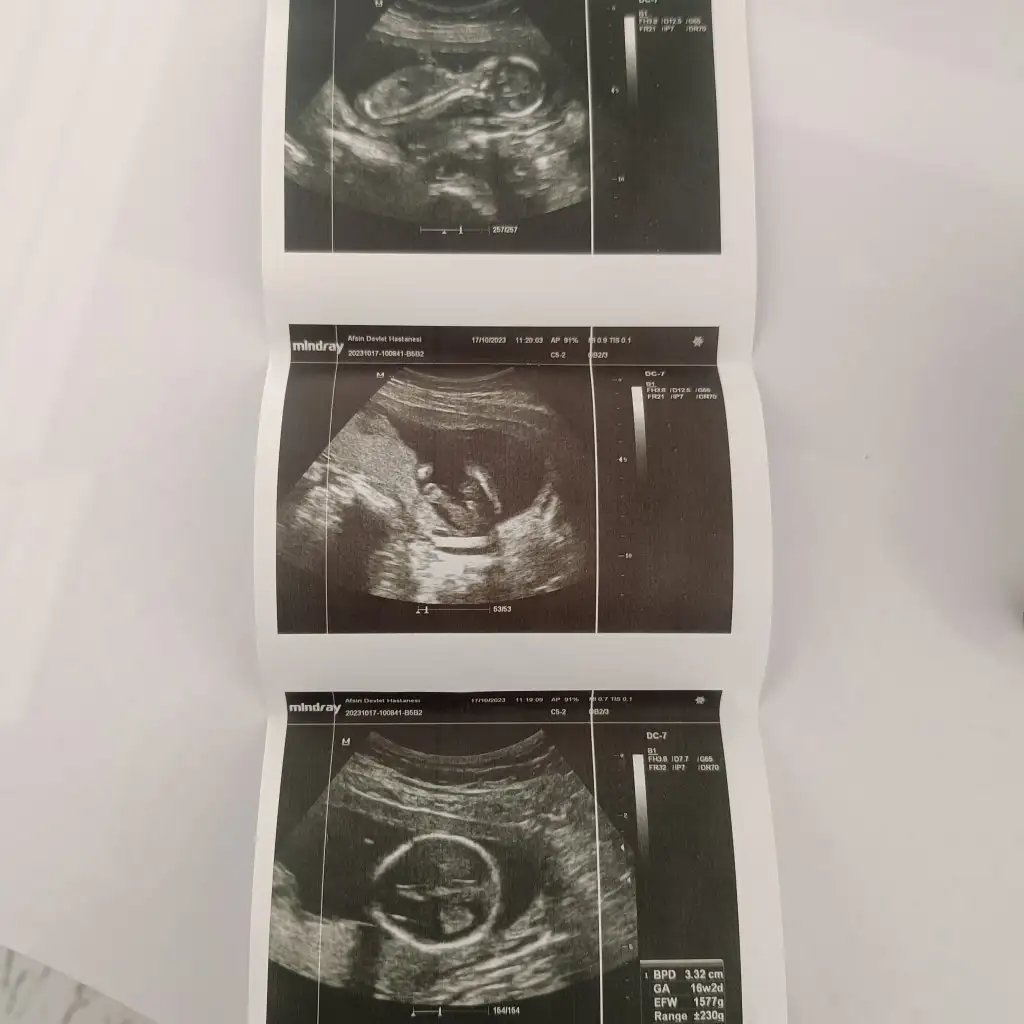

Kızlar bu ultrason terimleri nedir hangisi bebeğin ağırlığı hangisi boyu Googledan bakıyorum range de efw de ağırlık ama kafam karıştı

• IMG_20231017_120658.webp

32,9 KB · Görüntüleme: 64